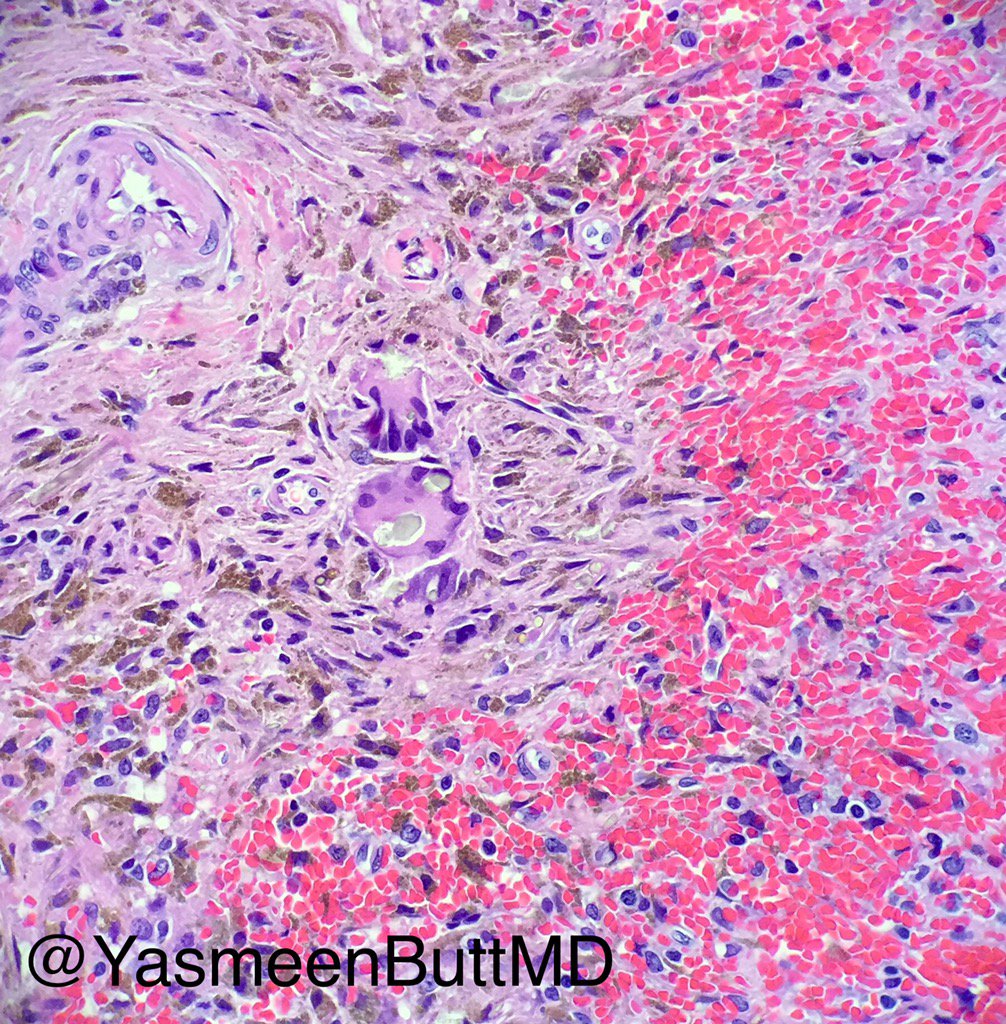

Twitter